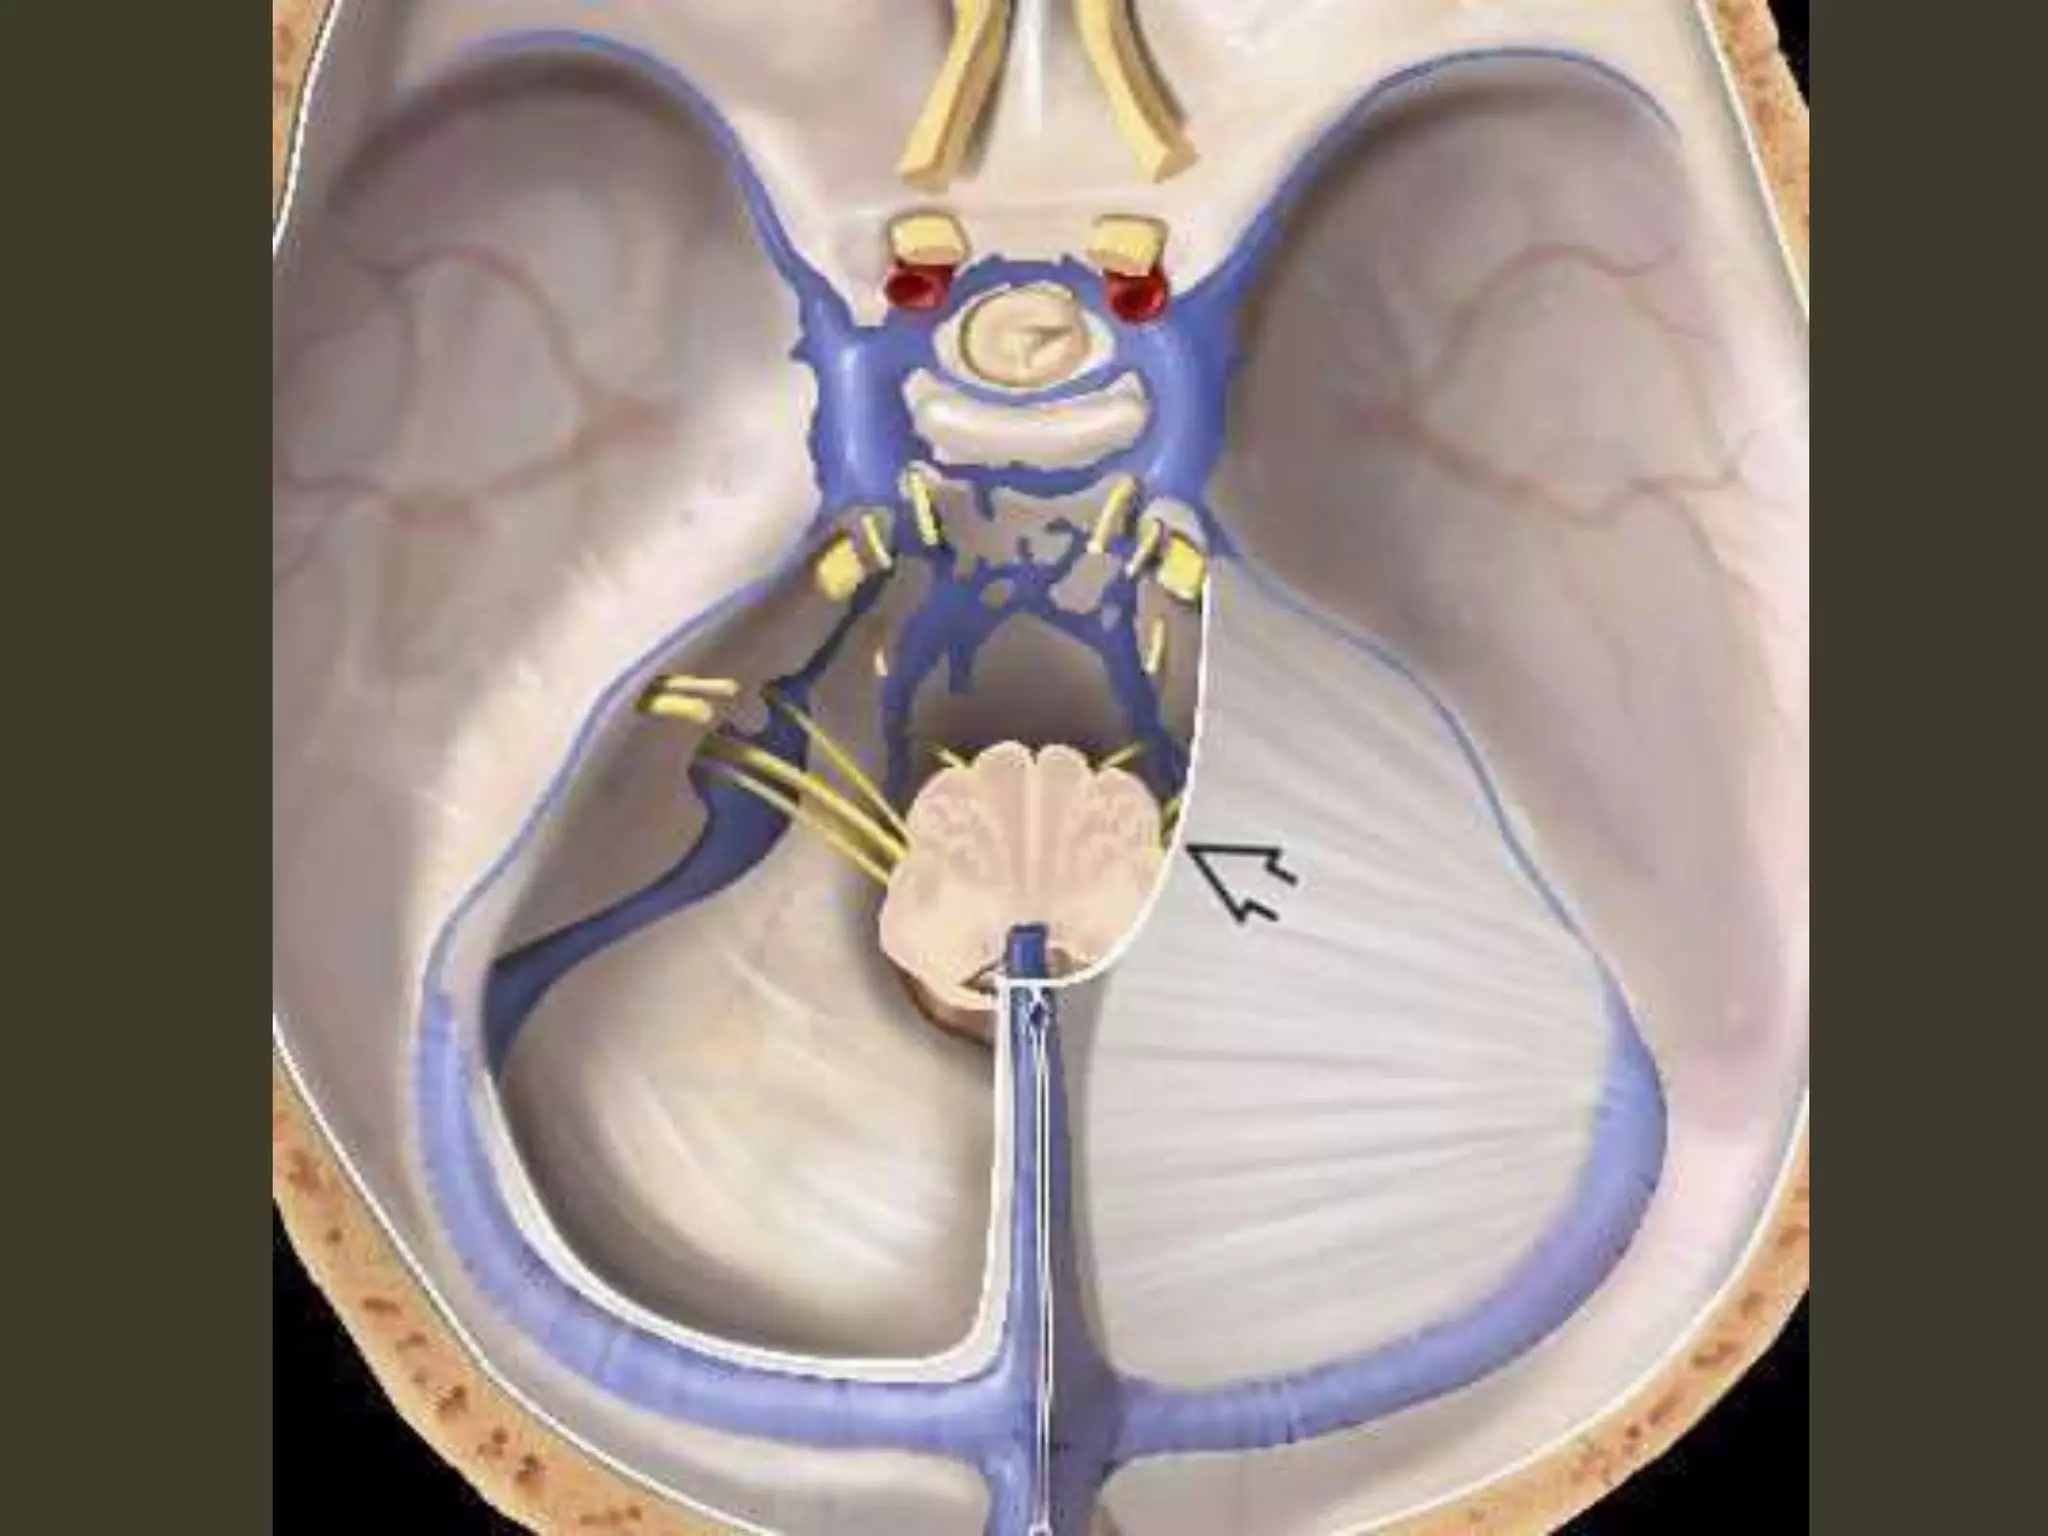

POSTERIOR FOSSA

MASS: TONSILLAR

HERNIATION

ASCENDING

Tonsillar herniation

• The cerebellar tonsils are displaced inferiorly

and become impacted into the foramen

magnum.

• congenital (e.g., Chiari 1 malformation)

– mismatch between size and content of the posterior

fossa

• Acquired

– an expanding posterior fossa mass pushing the tonsils

downward—more common

– intracranial hypotension: abnormally low intraspinal

CSF pressure

• tonsils are pulled downward

Tonsillar herniation: imaging

• Diagnosing tonsillar herniation on NECT scans

may be problematic.

Cisterna magna obliteration

• MR: much more easily diagnosed

• In the sagittal plane

– the tonsillar folia become vertically oriented

– the inferior aspect of the tonsils becomes

pointed

– Tonsils > 5 mm (or 7 mm in children) below the

foramen magnum are generally abnormal

• especially if they are peg-like or pointed (rather than

rounded)

• In the axial plane, T2 scans show that the

tonsils are impacted into the foramen

magnum

– obliterating CSF in the cisterna magna

– displacing the medulla anteriorly

Complications

•obstructive hydrocephalus

•tonsillar necrosis

ASCENDING TRANSTENTORIAL HERNIATION

•caused by any expanding posterior fossa mass

–Neoplasms > trauma

•Acute intraventricular obstructive

hydrocephalus

–caused by compression of the cerebral aqueduct